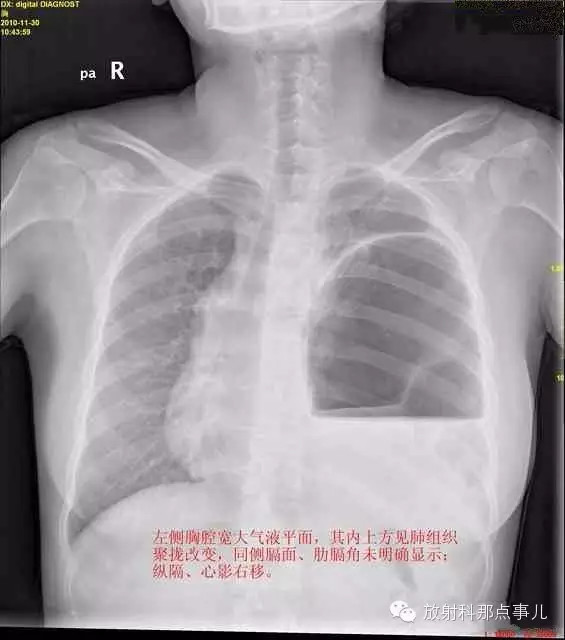

24岁,女性,腹痛渐加重并呕吐。

患者系顺产后18天产妇,产后感觉腹部疼痛不适,自认为正常反应,近两日因胸闷、腹部疼痛加剧伴呕吐来院就诊。

门诊腹部透视发现左侧胸腔巨大气液平面,为排除膈疝口服钡剂,但造影剂未见进入胃内。嘱住院,外科给予胃肠减压、补液等处理常规处理(未引流出明显气、液体)。5个半小时后再次检查,见少量造影剂进入消化道;为进一步了解情况,予泛影葡胺分别经胃管推注及口服,但均未进入胃内。当天进行外科急诊手术。

大部分胃、脾及横结肠均经过胸肋三角疝入左侧胸腔内,并见疝环形成。

考虑该患者因生产过程中腹压急剧升高,导致腹内脏器经膈肌缺损或薄弱部位进入胸腔内。